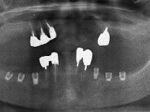

術前レントゲン